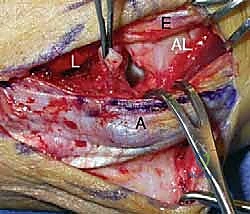

هذا المركب ليس مجرد خيط واحد، بل هو بنية تشريحية ثلاثية الأبعاد تتألف من أربعة مكونات رئيسية مترابطة:

- الرباط الزندي الجانبي الوحشي (Lateral Ulnar Collateral Ligament - LUCL): يُعرف أيضاً في بعض المراجع الطبية بالرباط الكعبري الزندي العضدي (RUHL). هذا الرباط هو "نجم العرض" والهدف الأساسي في أي عملية إعادة بناء. إنه المثبت الأقوى والأكثر أهمية ضد عدم الاستقرار الدوراني الخلفي الوحشي (PLRI). ينشأ هذا الرباط من نقطة محددة جداً على اللقمة الوحشية لعظم العضد (Lateral Epicondyle) ويمتد ليلتف حول رأس الكعبرة ويتصل بعمق وقوة في عرف العضلة الكابة للزند (Supinator Crest of the Ulna).

- الرباط الجانبي الكعبري الحقيقي (Radial Collateral Ligament - RCL): يقع هذا الرباط في الجزء الأمامي من المركب، ووظيفته الأساسية هي مقاومة إجهاد التقوس (Varus stress)، أي القوى التي تحاول طي الساعد للداخل.

- الرباط الحلقي (Annular Ligament): عبارة عن حلقة ليفية قوية تلتف حول رأس عظمة الكعبرة، وتعمل على تثبيت المفصل الكعبري الزندي القريب، مما يسمح للساعد بالدوران (الكب والاستلقاء) دون أن تنخلع الكعبرة.

- الرباط الجانبي الإضافي (Accessory Collateral Ligament): رباط مساعد يساهم في الاستقرار العام للمفصل الكبسولي.